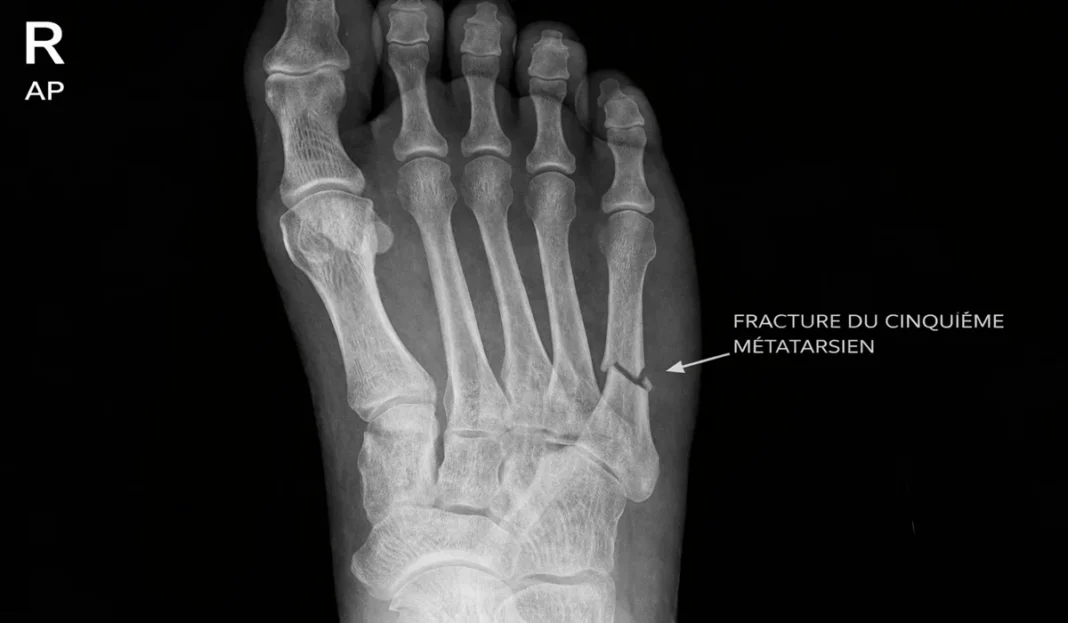

Radiographic evaluation plays a crucial role in the diagnosis of metatarsal fractures. Standard views of the foot, including an anteroposterior view, a 45-degree oblique view, and a lateral projection, are usually performed. To diagnose stress fractures, weight-bearing radiographs, including a lateral view of the foot and a tangential view of the metatarsal heads, may be helpful.

- Radiographs, including anteroposterior, 45-degree oblique, and lateral views, are essential to confirm the diagnosis, locate the fracture, and assess its severity.

Radiographic signs

Radiographic signs of metatarsal fractures play a crucial role in diagnosis, classification and treatment planning. Radiographic imaging allows detailed visualization of the metatarsal bones, fractured fragments and possible complications. Here are the main radiographic signs to consider when evaluating metatarsal fractures:

- Visible Fractures:

- Anteroposterior, 45-degree oblique, and lateral radiographs provide a complete view of the metatarsal bones, allowing detection of obvious fractures.

- Movement of Bone Fragments:

- X-rays reveal the degree of displacement of the bone fragments. Significant displacement may require surgery to restore alignment.

- Fracture Line:

- The fracture line is often visible on x-rays and can indicate the direction of the traumatic force. It is crucial for the classification of the fracture.